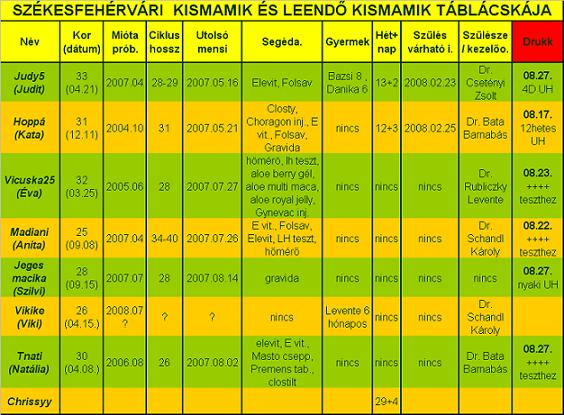

Ha valaki nem tudná "kiolvasni", mit lát, segítek: az első képen a drágánk feje jobb ldalt (a másikon is

) , aztán a kis teste, a cicije felett a pici folt az egyik keze, aztán egy nagy pocak, majd valahogy a lábai (egy pár lábujjacskája látható!

)

A másik képenközelebbről van a buksija, lehet látni a nóziját, meg az éppen csókra álló száját!!

Ja, és amikor uh-zott a doki, kitátotta a száját, vissza is játszotta BB, mondta, hogy tök érdekes, még ilyen pici, és nyitogatja a száját! Hát egész nap vigyorogtunk, úgy örültünk! Tényleg nagyon jó volt látni!

Ő a kisfiúnk, csak így tudtuk lefotózni, ennél jobban nem mutatta a kis pofiját.

Ő a kisfiúnk, csak így tudtuk lefotózni, ennél jobban nem mutatta a kis pofiját.